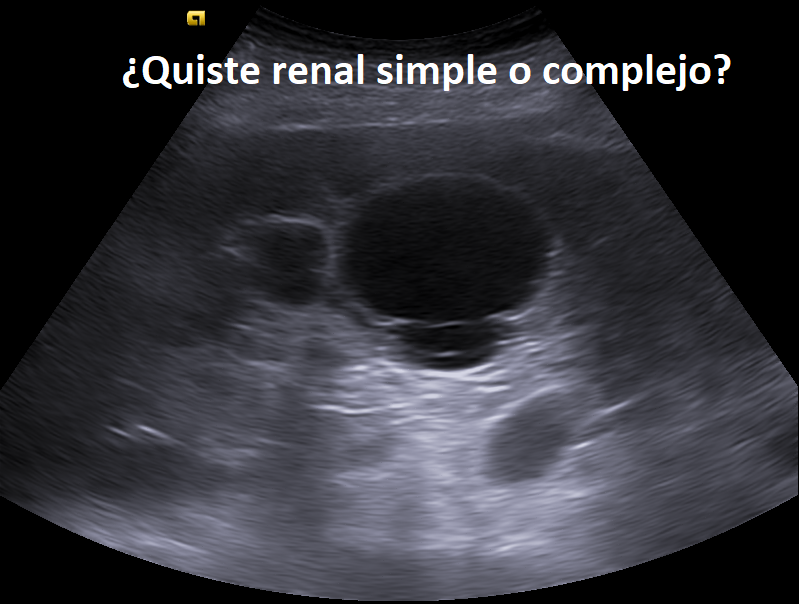

Compañeros de la ecografía clínica, si encontráis esto como hallazgo incidental, ¿cómo lo catalogaríais?

¿Quiste renal simple o complejo?

#POCUS #Ecosemfyc

@EcosemfyC Quiste renal complejo, ya que sus bordes no son regulares y tiene elementos ecogénicos en su interior